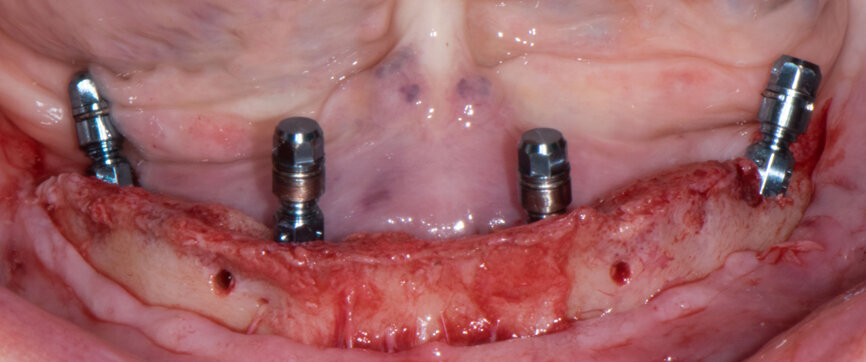

Implant beds were prepared (Figs. 13 & 14) and Straumann BLT implants placed with a torque setting of more than 35 Ncm, following the protocol to allow correct subsequent screw retained abutment placement (Figs. 15 & 16). Bone around the implants was prepared with bone profilers (Straumann) for the same reason (Fig. 17). The crest was flattened (Figs. 18 & 19), screw-retained abutments were screwed to 35 Ncm (Fig. 20) and covered with healing caps, and the wound was sutured (Fig. 21).